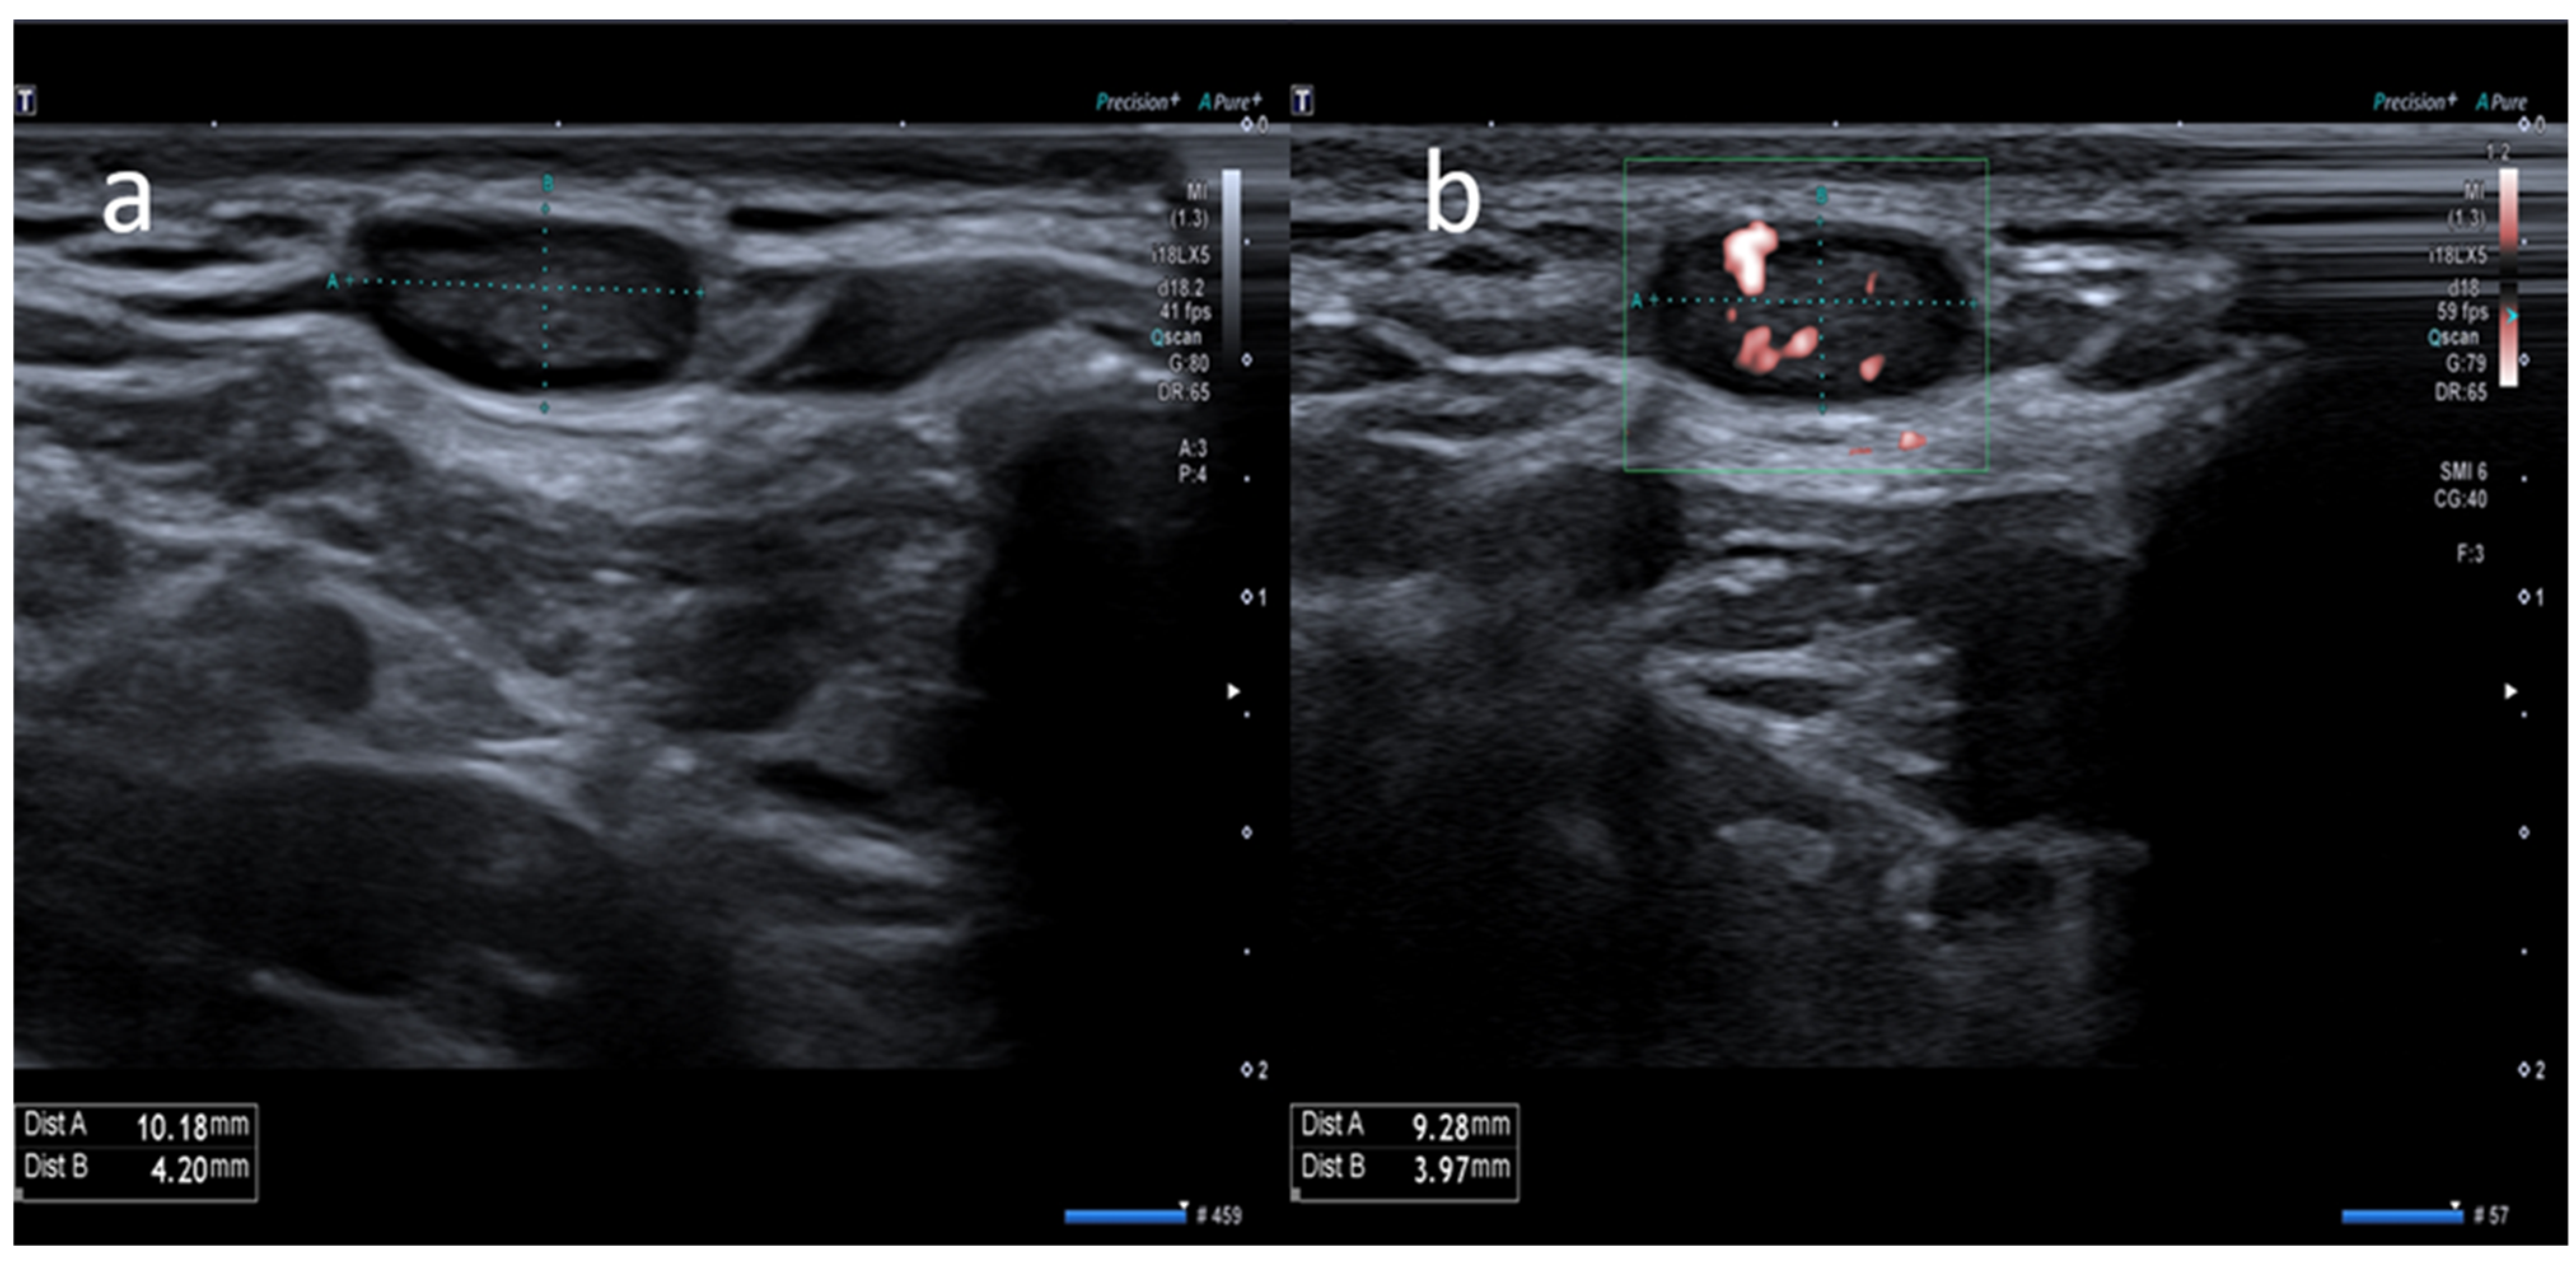

- Cocco, G.; Pizzi, A.D.; Fabiani, S.; Cocco, N.; Boccatonda, A.; Frisone, A.; Scarano, A.; Schiavone, C. Lymphadenopathy after the Anti-COVID-19 Vaccine: Multiparametric Ultrasound Findings. Biology 2021, 10, 652. [Google Scholar] [CrossRef] [PubMed]